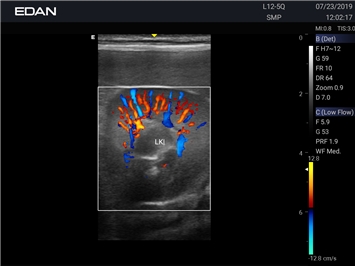

Цветовой допплер:

Да

Энергетический допплер: